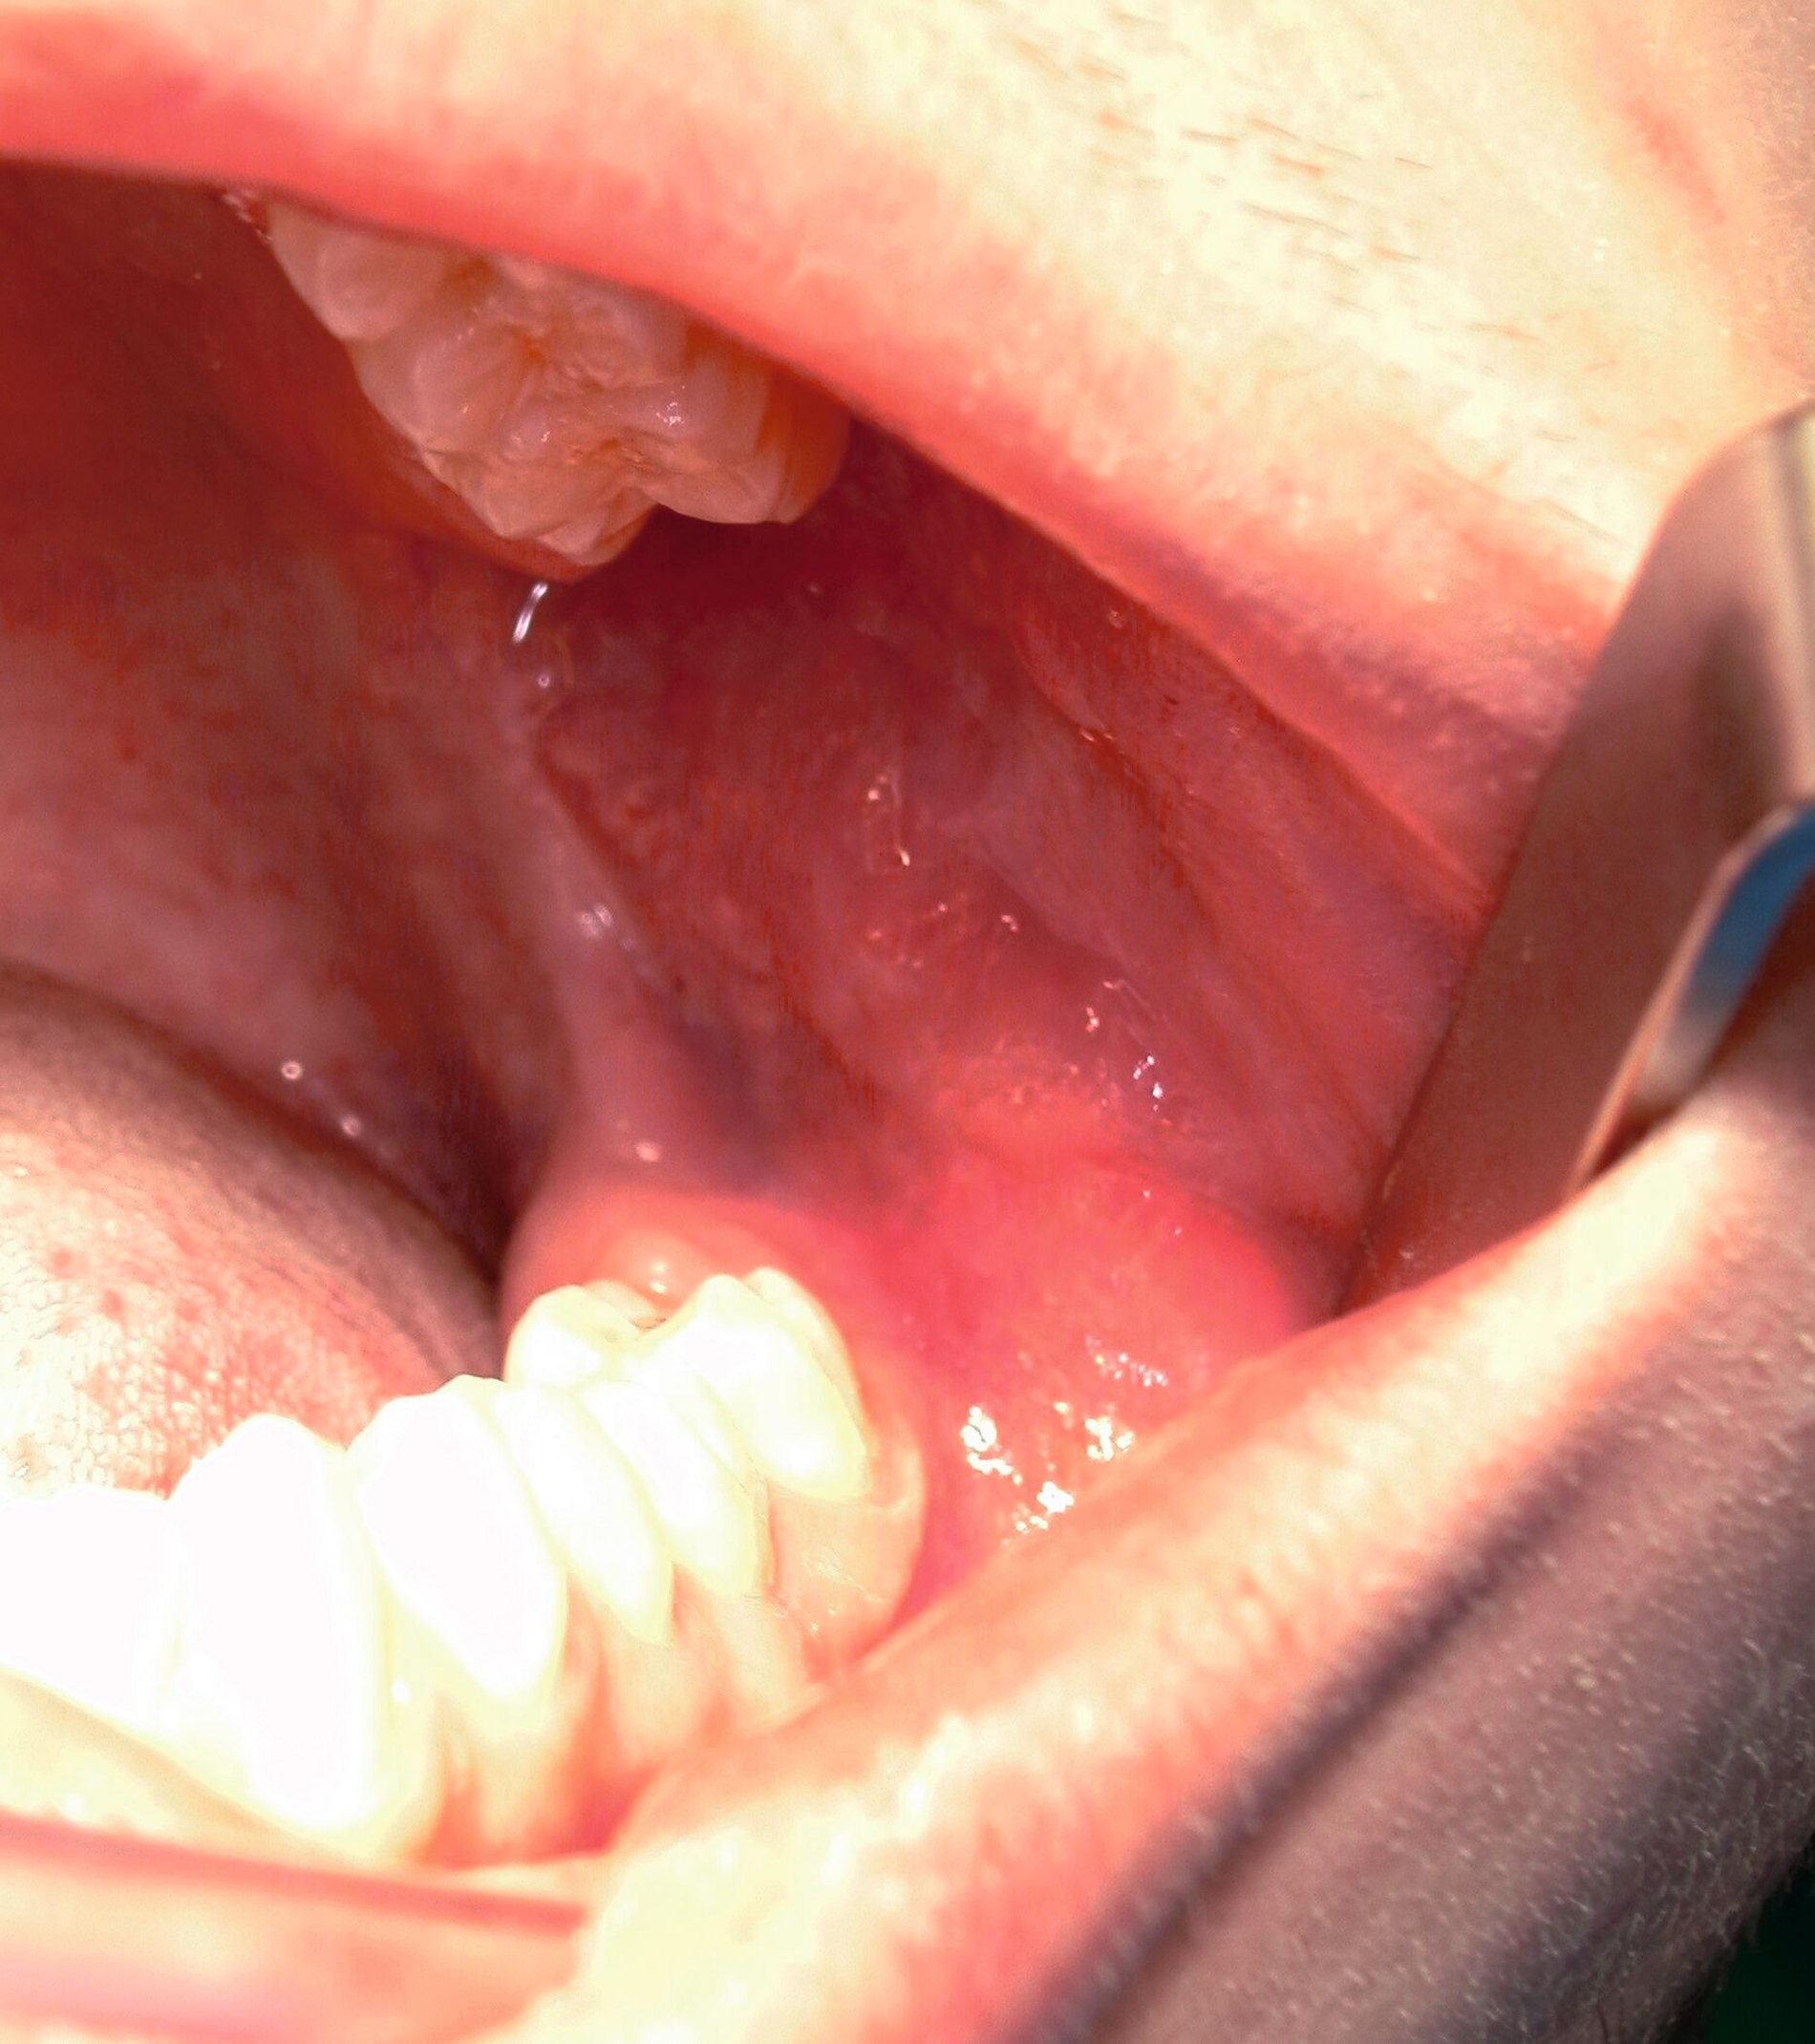

Zur Entfernung der Weisheitszähne im Oberkiefer wird zunächst der Kopf des Patienten etwas überstreckt, um eine bessere Übersicht zu erlangen. Bei der Bildung des Mukoperiostlappens geht man ähnlich vor wie im Unterkiefer: Die Schnittführung erfolgt distal entlang des Tubers auf den zweiten Oberkiefermolaren zu, dann marginal weiter bis mesial des zweiten Oberkiefermolaren [Gutwald et al., 2019; Schwenzer, 2019] (Abbildung 13).

Nach Darstellung des Knochens kann der Weisheitszahn meist schon mit dem Hebel anluxiert oder mittels rotierendem Instrument freigelegt werden. Dabei muss möglichst oberhalb des Zahnäquators angesetzt werden, sonst kann der Zahn in die Kieferhöhle oder in das umliegende Weichgewebe luxieren. Anschließend erfolgen die Kürettage, die Entfernung des Zahnsäckchens, der Knochenkanten und des Granulationsgewebes sowie die Prüfung einer Mund-Antrum-Verbindung (MAV) mittels Bowman-Sonde. Bei positiver Testung erfolgt die plastische Deckung mittels Mukoperiostlappen oder bei ausgedehnteren Defekten mittels Bichat-Fettpfropf (Abbildungen 14 und 15) [Gutwald et al., 2019; Schwenzer, 2019].